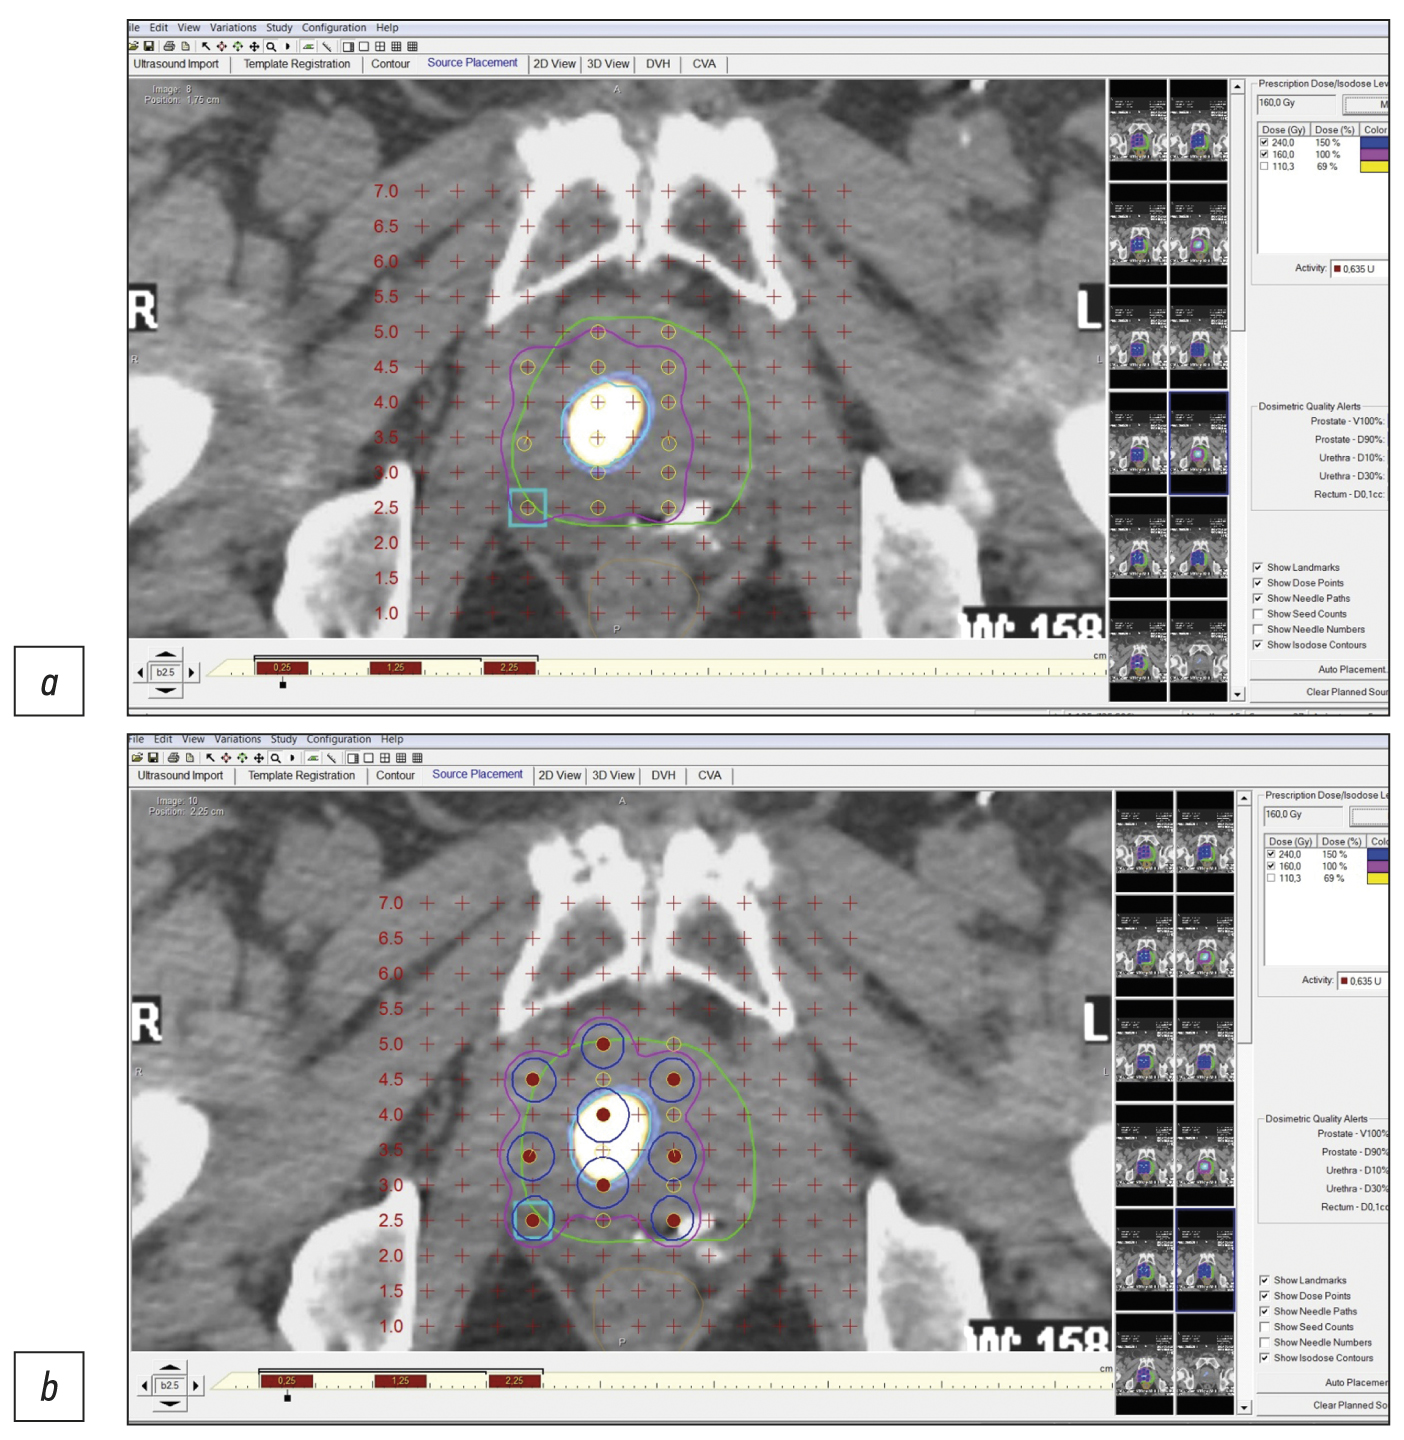

治疗无腺囊萌发迹象和无转移迹象(cT1-T2N0M0期)的局部前列腺癌的方法之一是植入基于同位素125I的微源近距离照射。结构成像方法(超声检查、电子计算机断层扫描(CT)、磁共振成像(MRI))在前列腺癌的鉴别诊断中特异性不高。混合放射成像技术(单光子发射计算机断层扫描+电子计算机断层扫描,SPECT/CT;正电子发射计算机断层扫描+电子计算机断层扫描,PET/CT;正电子发射断层扫描+磁共振成像,PET/MRI)结合了结构成像的横断面方法(CT和MRI)的高灵敏度和分子成像方法(SPECT、PET)的高特异性与肿瘤放射治疗物的优点。

在这项研究中,7例局部前列腺癌(格里森评分为6-7分)的临床观察结果表明了,通过使用PSMA受体(前列腺特异性膜抗原)分子成像(SPECT/CT、PET/CT)的混合方法,可以提高使用微源125I对局部前列腺癌进行低剂量近距离照射以及靶向活检的精确度。SPECT/CT比PET/CT更经济实惠,而且在存在冷试剂盒(HYNIC-PSMA)的情况下,允许在任何拥有适当扫描仪的放射性同位素诊断实验室进行检查。

混合分子成像控制下的PSMA引导活检和近距离照射创新技术可用于原发性和复发性的局部前列腺癌病例,提高准确度,减少检查创伤性,提高微源125I低剂量近距离照射的医疗和经济效益。